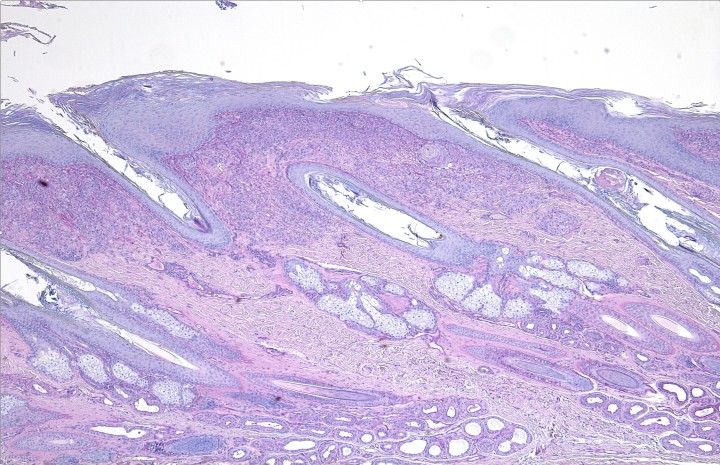

El estudio histológico obtuvo resultados similares en todas las muestras cutáneas. La epidermis mostraba hiperplasia irregular con hiperqueratosis ortoqueratótica y, en la muestra correspondiente a la nariz, se apreciaba una amplia ulceración. La dermis superficial, en especial la zona interfolicular, presentaba un infiltrado inflamatorio denso con predominio de macrófagos, junto con algunos polinucleares neutrófilos y focos linfoplasmocíticos en los que se observaban formaciones esféricas y filamentosas compatibles con formas fúngicas (hifas segmentadas y no pigmentadas). Las tinciones de Grocott y PAS resultaron positivas. El diagnóstico fue de una dermatitis piogranulomatosa de etiología fúngica (feohifomicosis, hialohifomicosis o micosis subcutánea) (Figs. 6-8).

<p>Corte histológico de la piel nasal. Se aprecia hiperplasia epidérmica y un infiltrado inflamatorio difuso en la dermis superficial. PAS x100.</p>

Corte histológico de la piel nasal. Se aprecia hiperplasia epidérmica y un infiltrado inflamatorio difuso en la dermis superficial. PAS x100.